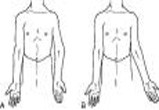

Sprengels1

Sprengel's shoulder-clin

Sprengel's shoulder-clin2